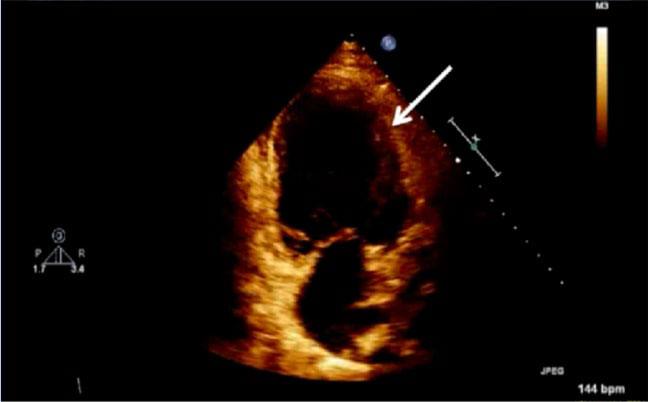

The exemption from the Institutional Review Board of Cleveland Clinic and consent from the patient were obtained for our case. A 42-year-old obese (body mass index 37.6 kg/m2) female at 38w2d, G2P1 with past medical history significant for gestational diabetes mellitus, presented with a three-day history of shortness of breath, orthopnea, chest tightness, tachycardia, headache, and swollen feet. She denied fever, vision changes, and right upper abdominal pain. No history of cardiac diseases or chronic hypertension was reported. Her vital signs included blood pressure (BP) of 145/98 mmHg, respiratory rate of 30 breaths per minute, heart rate of 150 beats per minute (bpm), and blood oxygen saturation (SpO2) of 98% on 10 liters per minute of oxygen through a non-rebreather mask. She was afebrile. Physical exam revealed loud S3 gallop, bilateral basilar rhonchi, and bilateral feet and ankle edema. Fetal monitoring was normal with a heart rate of 125 bpm. Laboratory results showed a white blood cell count of 12.8 k/µL, urine protein of 74 mg/dl, NT-proBNP of 1017 pg/ml, mildly elevated aspartate transaminase of 45 U/L and alanine transaminase of 30 U/L, and normal troponin. Electrocardiogram reported sinus tachycardia with borderline LV hypertrophy and frequent premature ventricular contractions (PVCs). Chest X-ray showed bilateral basilar infiltration. Echocardiogram revealed dilated LV with severely decreased function, EF of 25%, diffuse LV hypokinesia, and normal right ventricle function (Figure 1 and Figure 2). The patient started contractions and labor analgesia was administered through the epidural catheter; BP was noted to be 118/62 mmHg. Coagulation profile was normal. She was admitted to the intensive care unit (ICU) and Swan Ganz catheter, central, and arterial lines were inserted to monitor hemodynamics and heart function. Although our patient's clinical symptoms may lead us to consider preeclampsia, we ruled out preeclampsia because her labs did not meet criteria for diagnosis. Our patient was diagnosed with PPCM, for which she was placed on intravenous (IV) furosemide, tocolytic medication, and digoxin. Tocolytic medication was given to delay delivery until heart function improved, as the patient was unable to lie flat and EF was very low.

Figure 1: Echocardiogram of apical four chamber view of the heart showing dilated left ventricle and reduced ejection fraction; LV: left ventricle, EF: ejection fraction, A4C: apical four chamber, Vol: volume.

Figure 2: Echocardiogram of apical four chamber view of the heart, depicting left ventricular wall hypertrophy (white arrow).